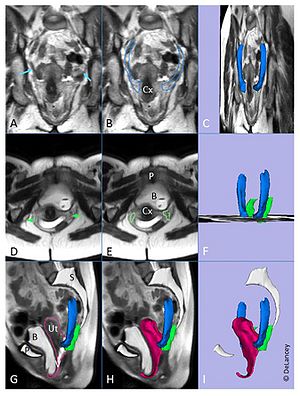

- 3.10 Posterior Vaginal Prolapse Shape and Position Changes at Maximal Valsalva Seen in 3D MRI-based Models

- 3.17 Levator Ani Subtended Volume: A Novel Parameter to Evaluate Levator Ani Muscle Laxity in Pelvic Organ Prolapse